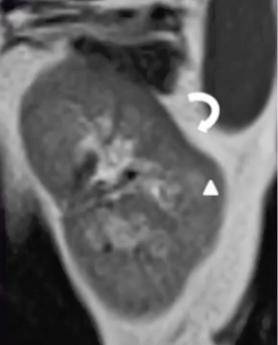

驼峰肾,马蹄肾,煎饼肾.肾脏结构异常 ct 图像,你都认识吗?